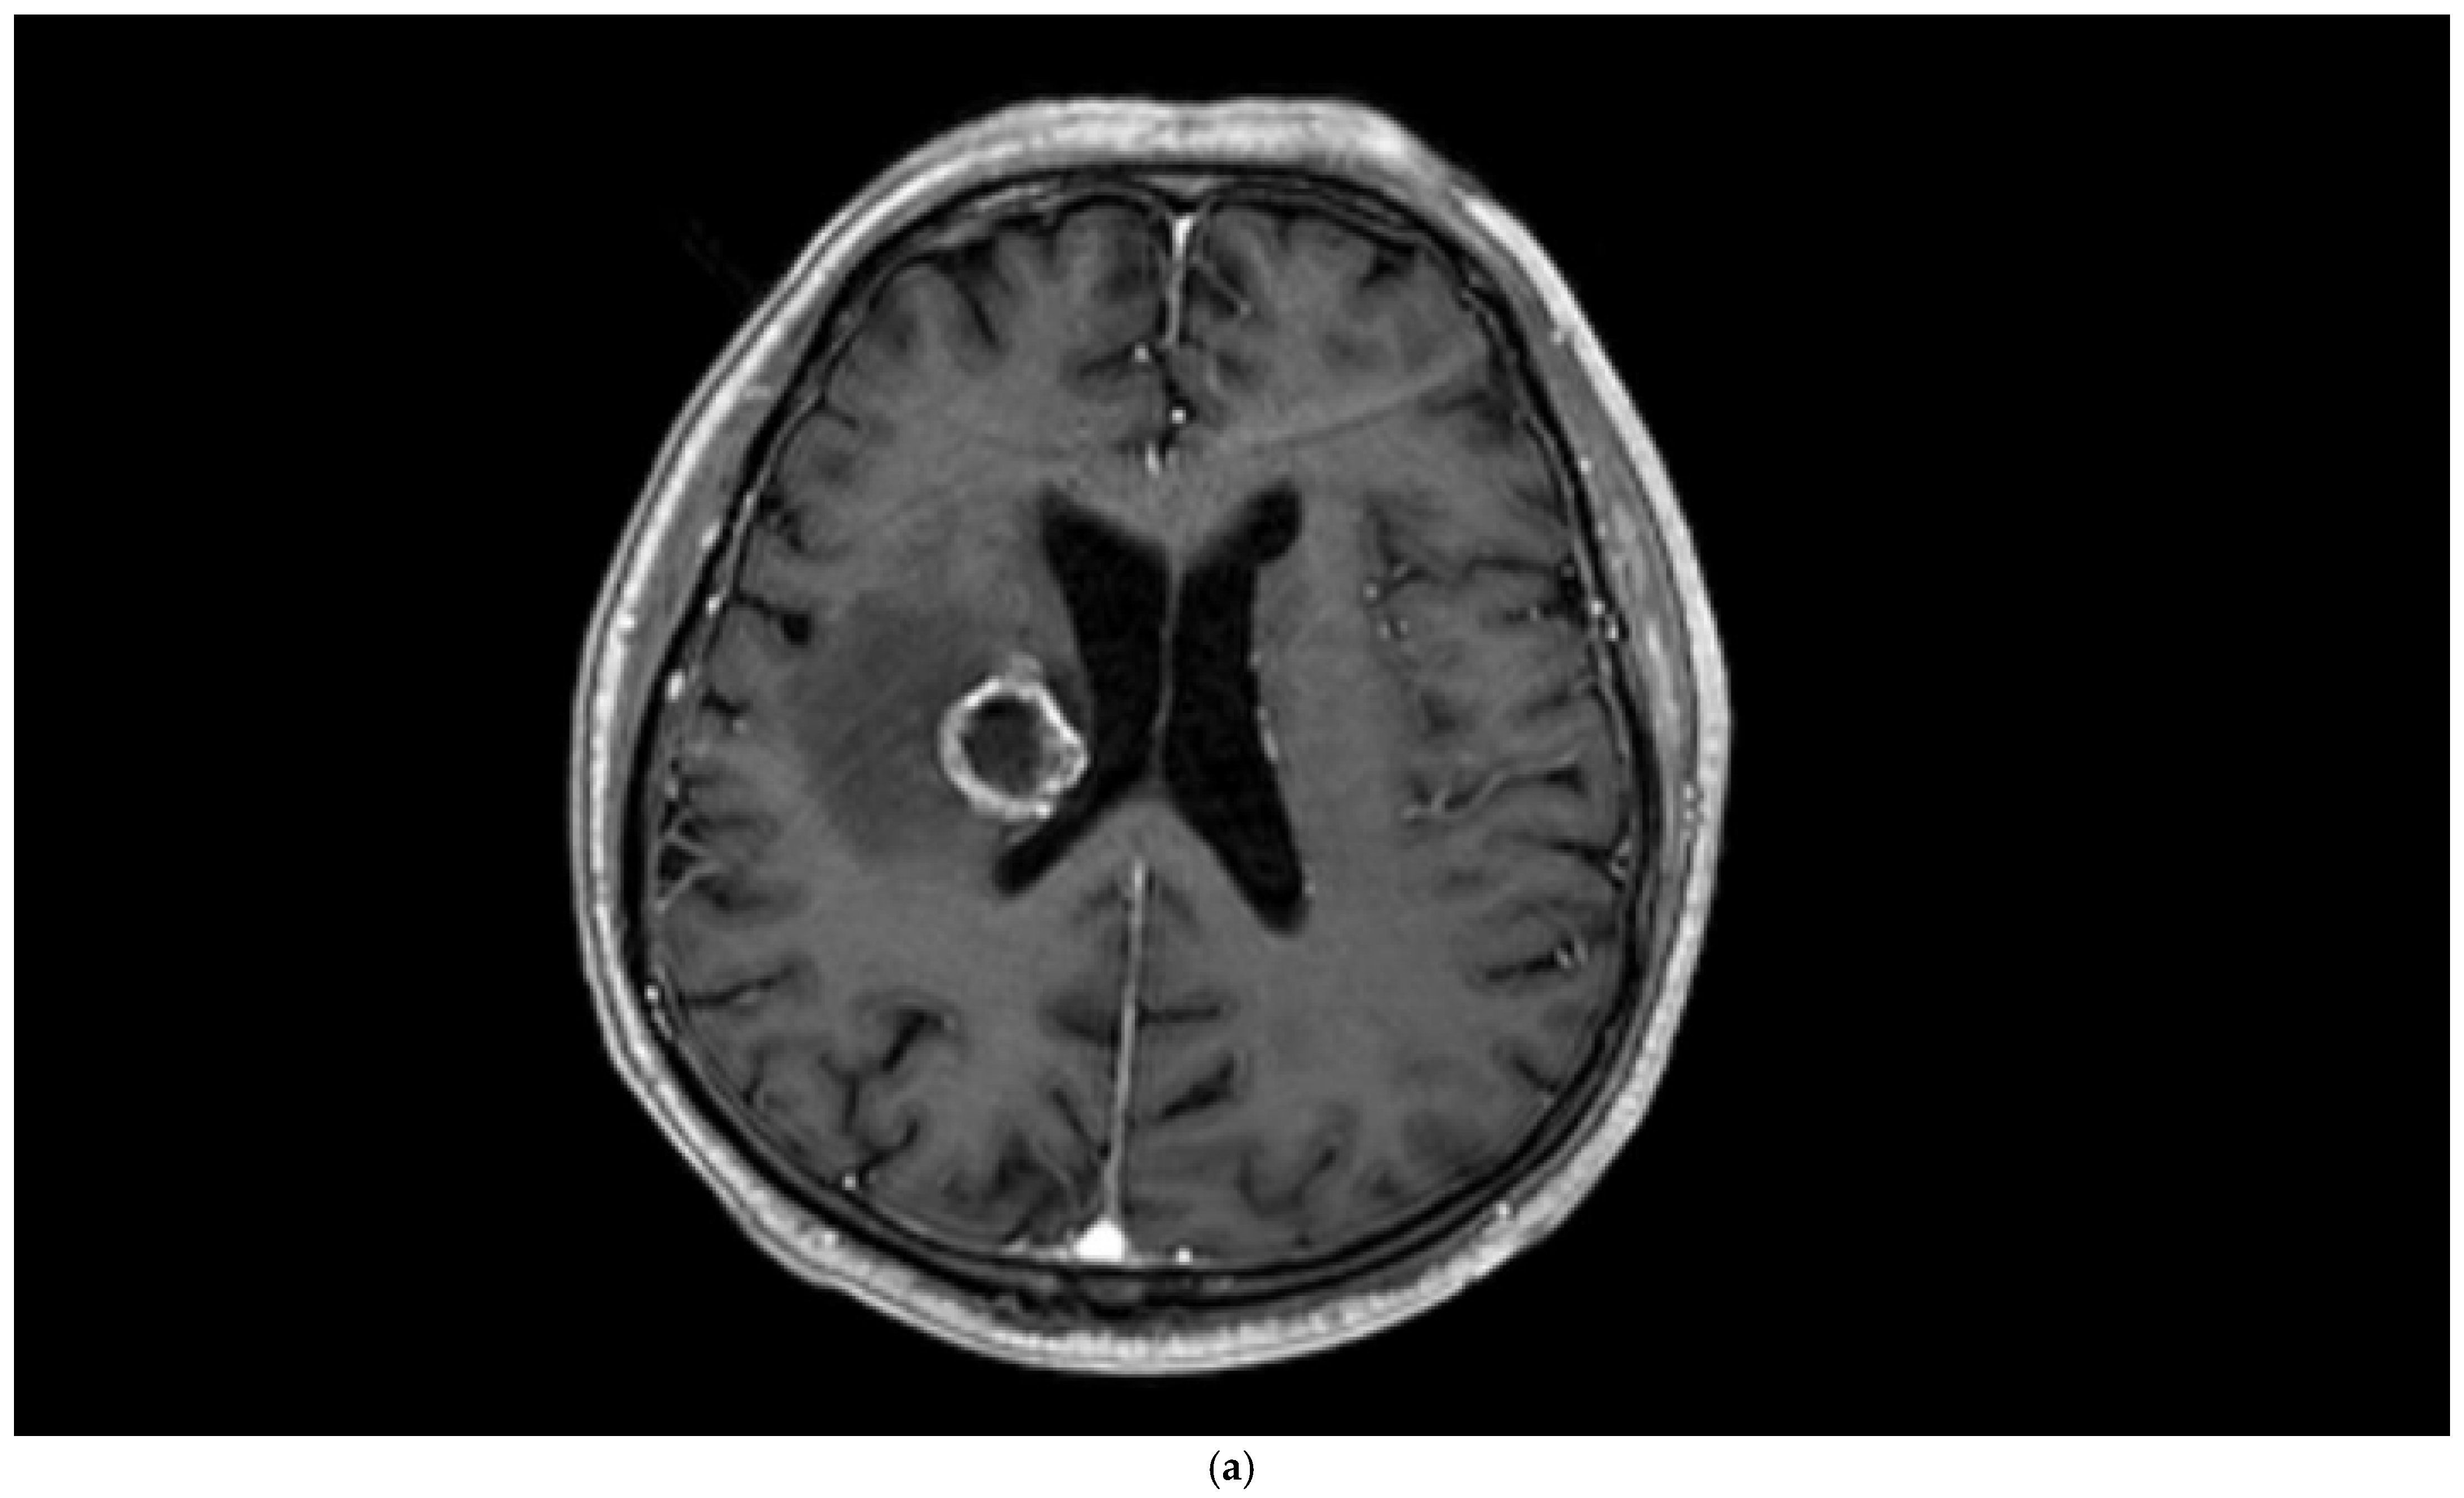

Figure 2. Brain magnetic resonance imaging (MRI) of a 67-year-old male with small-cell lung carcinoma revealed (a) peripherally enhanced right periventricular mass on post-contrast axial T1-weighted image and (b) hyperperfusion with a rCBV of 2.4 in perfusion-weighted imaging. Pink ROI is from metastatic nodule and white ROI is from contralateral parenchyma.